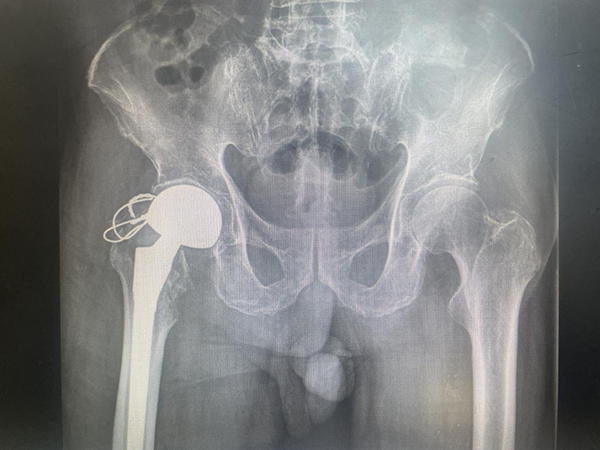

惠正廣團(tuán)隊(duì)為陳大爺制定了詳細(xì)而周密的中西醫(yī)結(jié)合的多學(xué)科聯(lián)合(MDT)診療方案,在麻醉科及手術(shù)室護(hù)理團(tuán)隊(duì)的精心配合下,手術(shù)非常成功。術(shù)后經(jīng)功能康復(fù),以及中醫(yī)藥特色技術(shù)的綜合治療,陳大爺終于可以下床活動(dòng)了。

●(術(shù)后X線片)